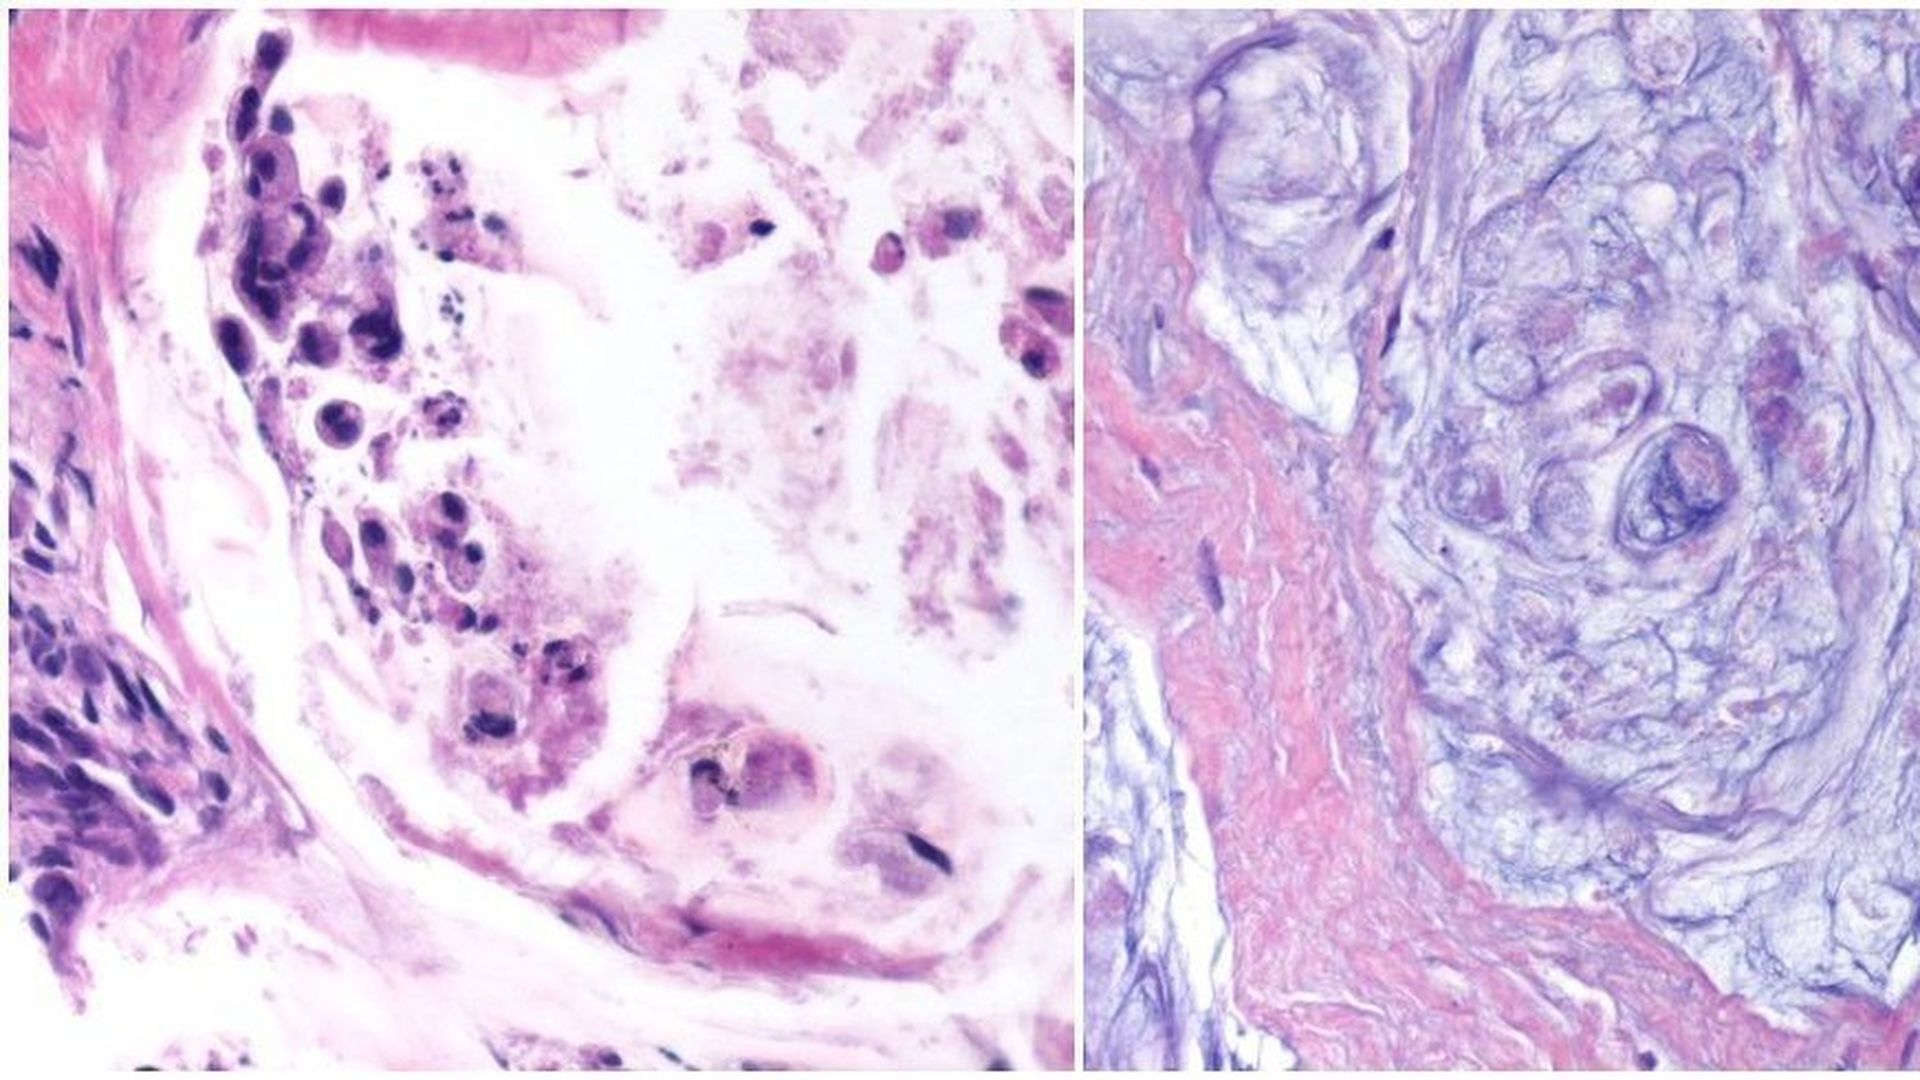

Live cancer before treatment (l)/ Dead cancer after treatment (r)